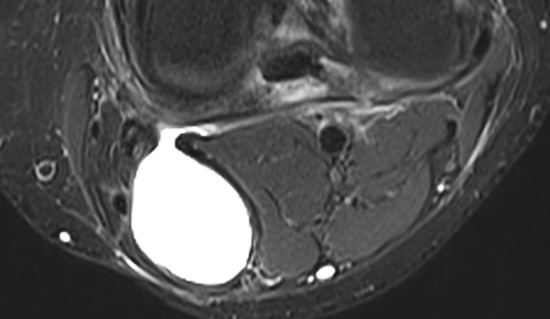

Kyste Synovial

- Vrai Kyste = Hernie de synoviale

- Communique avec l’articulation

- Lliquide articulaire

- Kyste de Baker = Le seul vrai kyste synovial globalement